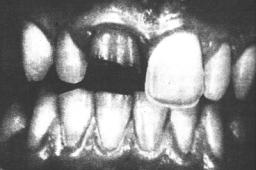

Сохранение электровозбудимости в пределах нормы при первом обращении не исключает возникновения воспаления и гибели пульпы на более поздних этапах, что может привести к изменению цвета коронки в дальнейшем (рис. 17).

Рис. 17:

Изменение цвета коронки после травмы зуба